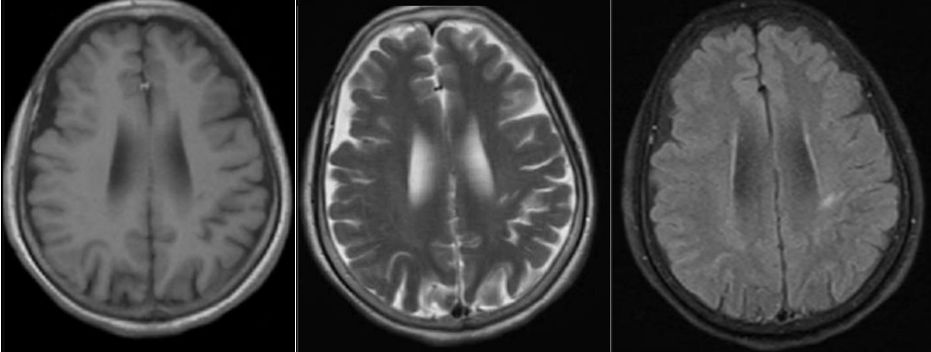

病例12

女性,75岁,发作性抽搐半月,意识障碍2天。

答案:抗GABABR抗体相关脑炎。抗GABABR抗体相关脑炎在临床上符合边缘性脑炎的表现,通常以癫痫发作、记忆力减退和意识障碍为主要特征。表现情势多样的癫痫发作是早期最突出的特征,多为继发性全身发作,还可以表现为复杂部分性发作、全面发作、全面强直-阵挛性发作、部分性运动性发作,甚至出现癫痫持续态势。患者多合并有记忆力减退和意识障碍,病程后期甚至出现幻觉和人格改变。癫痫发作也可以作为其唯一的表现。约有50%的GABABR抗体阳性患者合并小细胞肺癌,少数可合并其他肺部神经内分泌肿瘤、黑色素瘤及良性胸腺瘤等肿瘤。头MRI一侧或两侧内侧颞叶FLAIR/T2像信号增高提示该诊断的可能,但是这也见于其他自身免疫性脑炎。